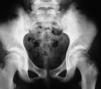

Se realizó analítica completa que incluyó hemograma, bioquímica con enzimas hepáticas, calcio, fósforo, fosfatasa alcalina, proteinograma, alfa-1-antitripsina, inmunoglobulinas y función renal, cuyos valores estuvieron dentro del rango de la normalidad. La velocidad de sedimentación globular (VSG) fue de 40 mm. La radiografía de tórax y la ecografía abdominal no evidenciaron alteraciones. En la radiografía de las sacroilíacas se observó una sacroilíaca izquierda con márgenes irregulares y mal definidos (fig. 1). En la gammagrafía con 99mTc se describió una lesión localizada en la sacroilíaca izquierda que deformaba y superaba esta articulación, con bordes abollonados hipercaptantes de forma moderada y áreas frías centrales. Se llevó a cabo una tomografía axial computarizada (TAC) de las sacroilíacas que puso de manifiesto alteraciones en la arquitectura trabecular del hueso ilíaco izquierdo con focos de lisis y esclerosis ósea adyacente a la articulación (fig. 2). En la resonancia magnética (RM) de las sacroilíacas se observaron cambios en la intensidad de la señal del componente medular de la pala ilíaca izquierda, con alternativa de hipo e hiperintensidad, y asimetría tenue de partes blandas con leve aumento de volumen en las zonas próximas al hueso sugestivo de proceso infiltrativo tumoral (fig. 3). En la TAC torácica se describió una imagen nodular en el lóbulo inferior izquierdo en los segmentos posteriores compatible con metástasis pulmonar. La biopsia de médula ósea no mostró signos de infiltración neoplásica. Se realizó una biopsia de la lesión que evidenció un tumor indiferenciado de célula redonda pequeña, con afección de hueso, periostio y músculo esquelético así como la presencia de fibrosis y desmoplasia estromal notables, sin signos de diferenciación. Los marcadores CD45, PAS, proteína S-100 y desmina fueron negativos. Se observó también manifiesta positividad de membrana para el anticuerpo CD-99 (O13), vimentina + + + y ENS (enolasa neuronal) + /-. Este patrón fue compatible morfológica, histoquímica e inmunocitoquímicamente con tumor de Ewing.

Figura 1. Radiografía de sacroilíacas. Se observa la sacroilíaca izquierda con márgenes irregulares y mal definidos.